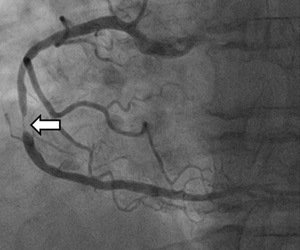

심근경색은 심장 근육에 혈액 공급이 부족하여 발생하는 질환으로, 심장 근육은 혈액을 공급받아야만 기능을 유지할 수 있는데, 혈관이 막히거나 좁아지면 혈액 공급이 부족해져 심장 근육이 죽게 됩니다. 그만큼 심근경색은 생명을 위협하는 질환이므로 무엇보다 조기 진단과 치료가 중요합니다.